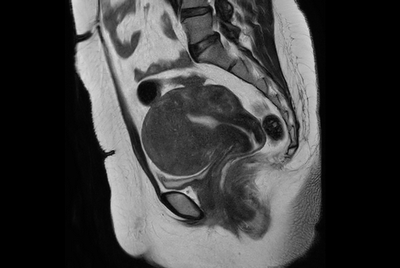

Prostate with dual coil set-up

Female pelvis with myoma (Compressed SENSE)